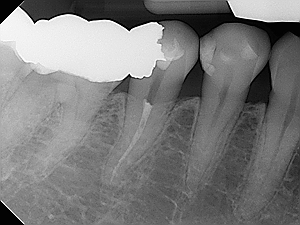

The procedure involves removing the pulp (the live tissue inside the tooth), cleaning and disinfecting root canals and then filling and sealing it.

• Root canals are calcified and are not accessible